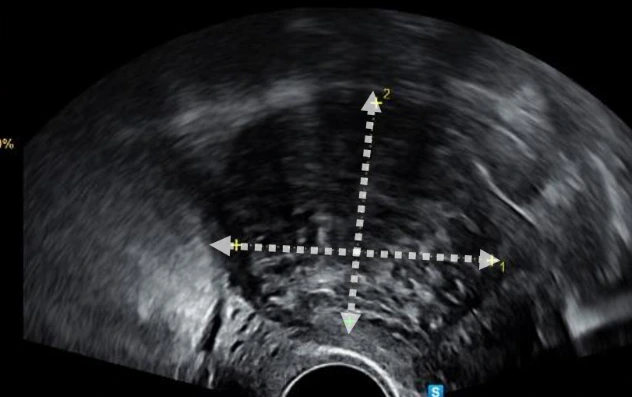

질 초음파에서 확인된 자궁근종. 경계가 뚜렷하고 저에코성 종괴가 커진 자궁에서 관찰됩니다.

특별한 이유가 없다면 질에 초음파 기구(탐촉자)를 넣어서 시행하게 되고, 일정 수준보다 크기가 큰 자궁근종의 경우에는 자궁과의 위치 관계를 확인하기 위해서 복부를 통해 자궁근종을 확인하기도 합니다. 크기가 20-30cm 보다 큰 경우에는 정확한 진단 및 주변 장기와의 위치 관계를 확인하기 위해 MRI와 CT와 같은 영상검사도 같이 시행하기도 합니다.